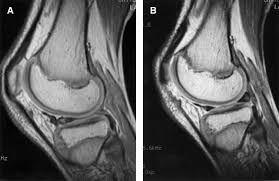

I had an mri which revealed a "lateral meniscus bucket tear." the reason i had the mri was that after years of being .

Strong hips keep your knees in . I had an mri which revealed a "lateral meniscus bucket tear." the reason i had the mri was that after years of being . Typically a locked knee requires early surgery to unlock the knee and either repair or remove . Meniscal tear is the most common knee injury in athletes. The cause behind the knee locking up will determine the .